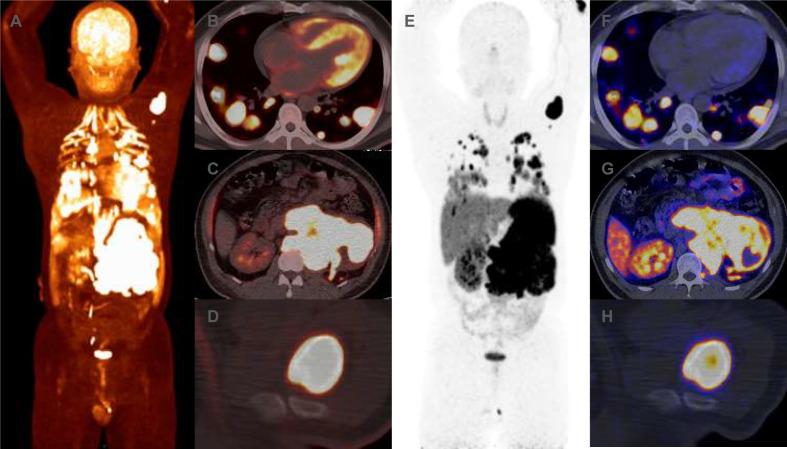

A 40-year-old male patient presented with recurrent hypoglycemia and hypertension crisis. Imaging revealed a huge left retroperitoneal tumor and multiple diffuse metastases in lungs. Catecholamine was also elevated, aligning with a diagnosis of metastatic PGL. Pathology also confirmed this diagnosis. Additionally, the immunohistochemistry indicated negative expression of SDHB and gene test showed somatic SDHB mutation. Given the SDHB mutation, cyclophosphamide-vincristine-dacarbazine (CVD) chemotherapy was initiated in critical conditions. Subsequently, a significant tumor shrinkage and complete biochemical response were observed after two treatment cycles. In September 2024, CT scan revealed new pulmonary lesions. The progression-free survival (PFS) with CVD chemotherapy was 24 months.

一名40岁男性患者出现反复低血糖和高血压危象。影像学检查显示左腹膜后有巨大肿瘤,肺部有多个弥漫性转移灶。儿茶酚胺水平也升高,符合转移性PGL的诊断。病理检查也证实了这一诊断。此外,免疫组化显示SDHB阴性表达,基因检测显示存在体细胞SDHB突变。鉴于SDHB突变,在危急情况下开始采用环磷酰胺-长春新碱-达卡巴嗪(CVD)化疗。随后,经过两个治疗周期后观察到肿瘤显著缩小且生化指标完全缓解。2024年9月,CT扫描显示肺部出现新病灶。CVD化疗的无进展生存期(PFS)为24个月。